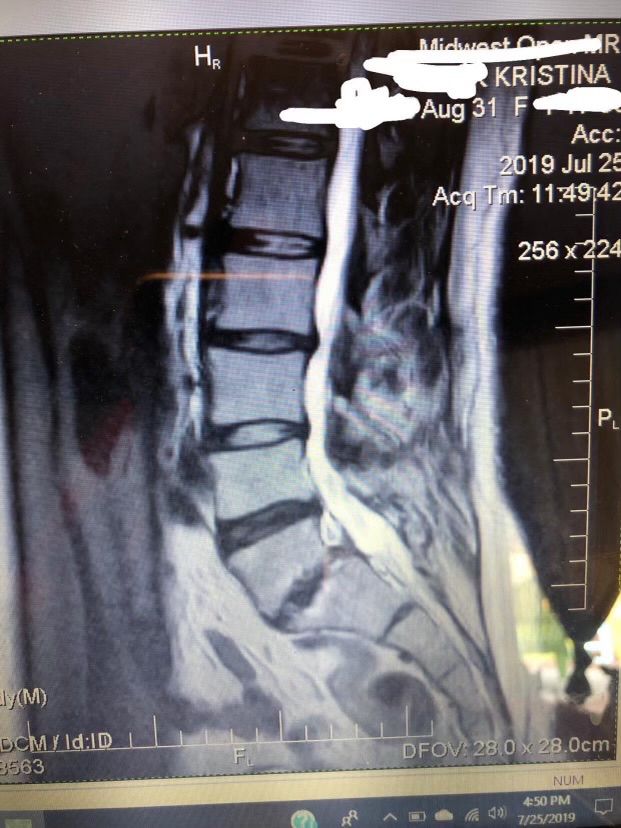

Yesterday was a bad day. I lost my job. My back had been very bad Since Saturday. Not to mention my son’s surgery coming up on the 9th &

My daughter’s on the 4th of December!

1st-picture is my MRI back in 19.

2nd- is my back with staples. Needless to say it could not sleep on my back for a min.